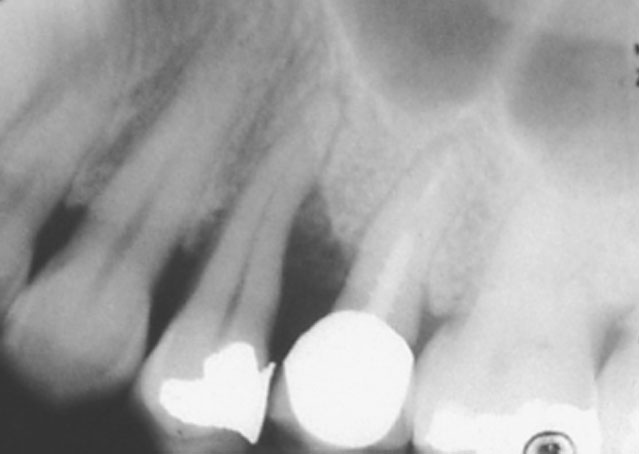

X-Rays

X-rays are used to diagnose bone loss surrounding the roots of the teeth. If evidence of bone loss is seen on x-rays periodontal treatment is mandatory. If left untreated the likelihood of tooth-loss is high.